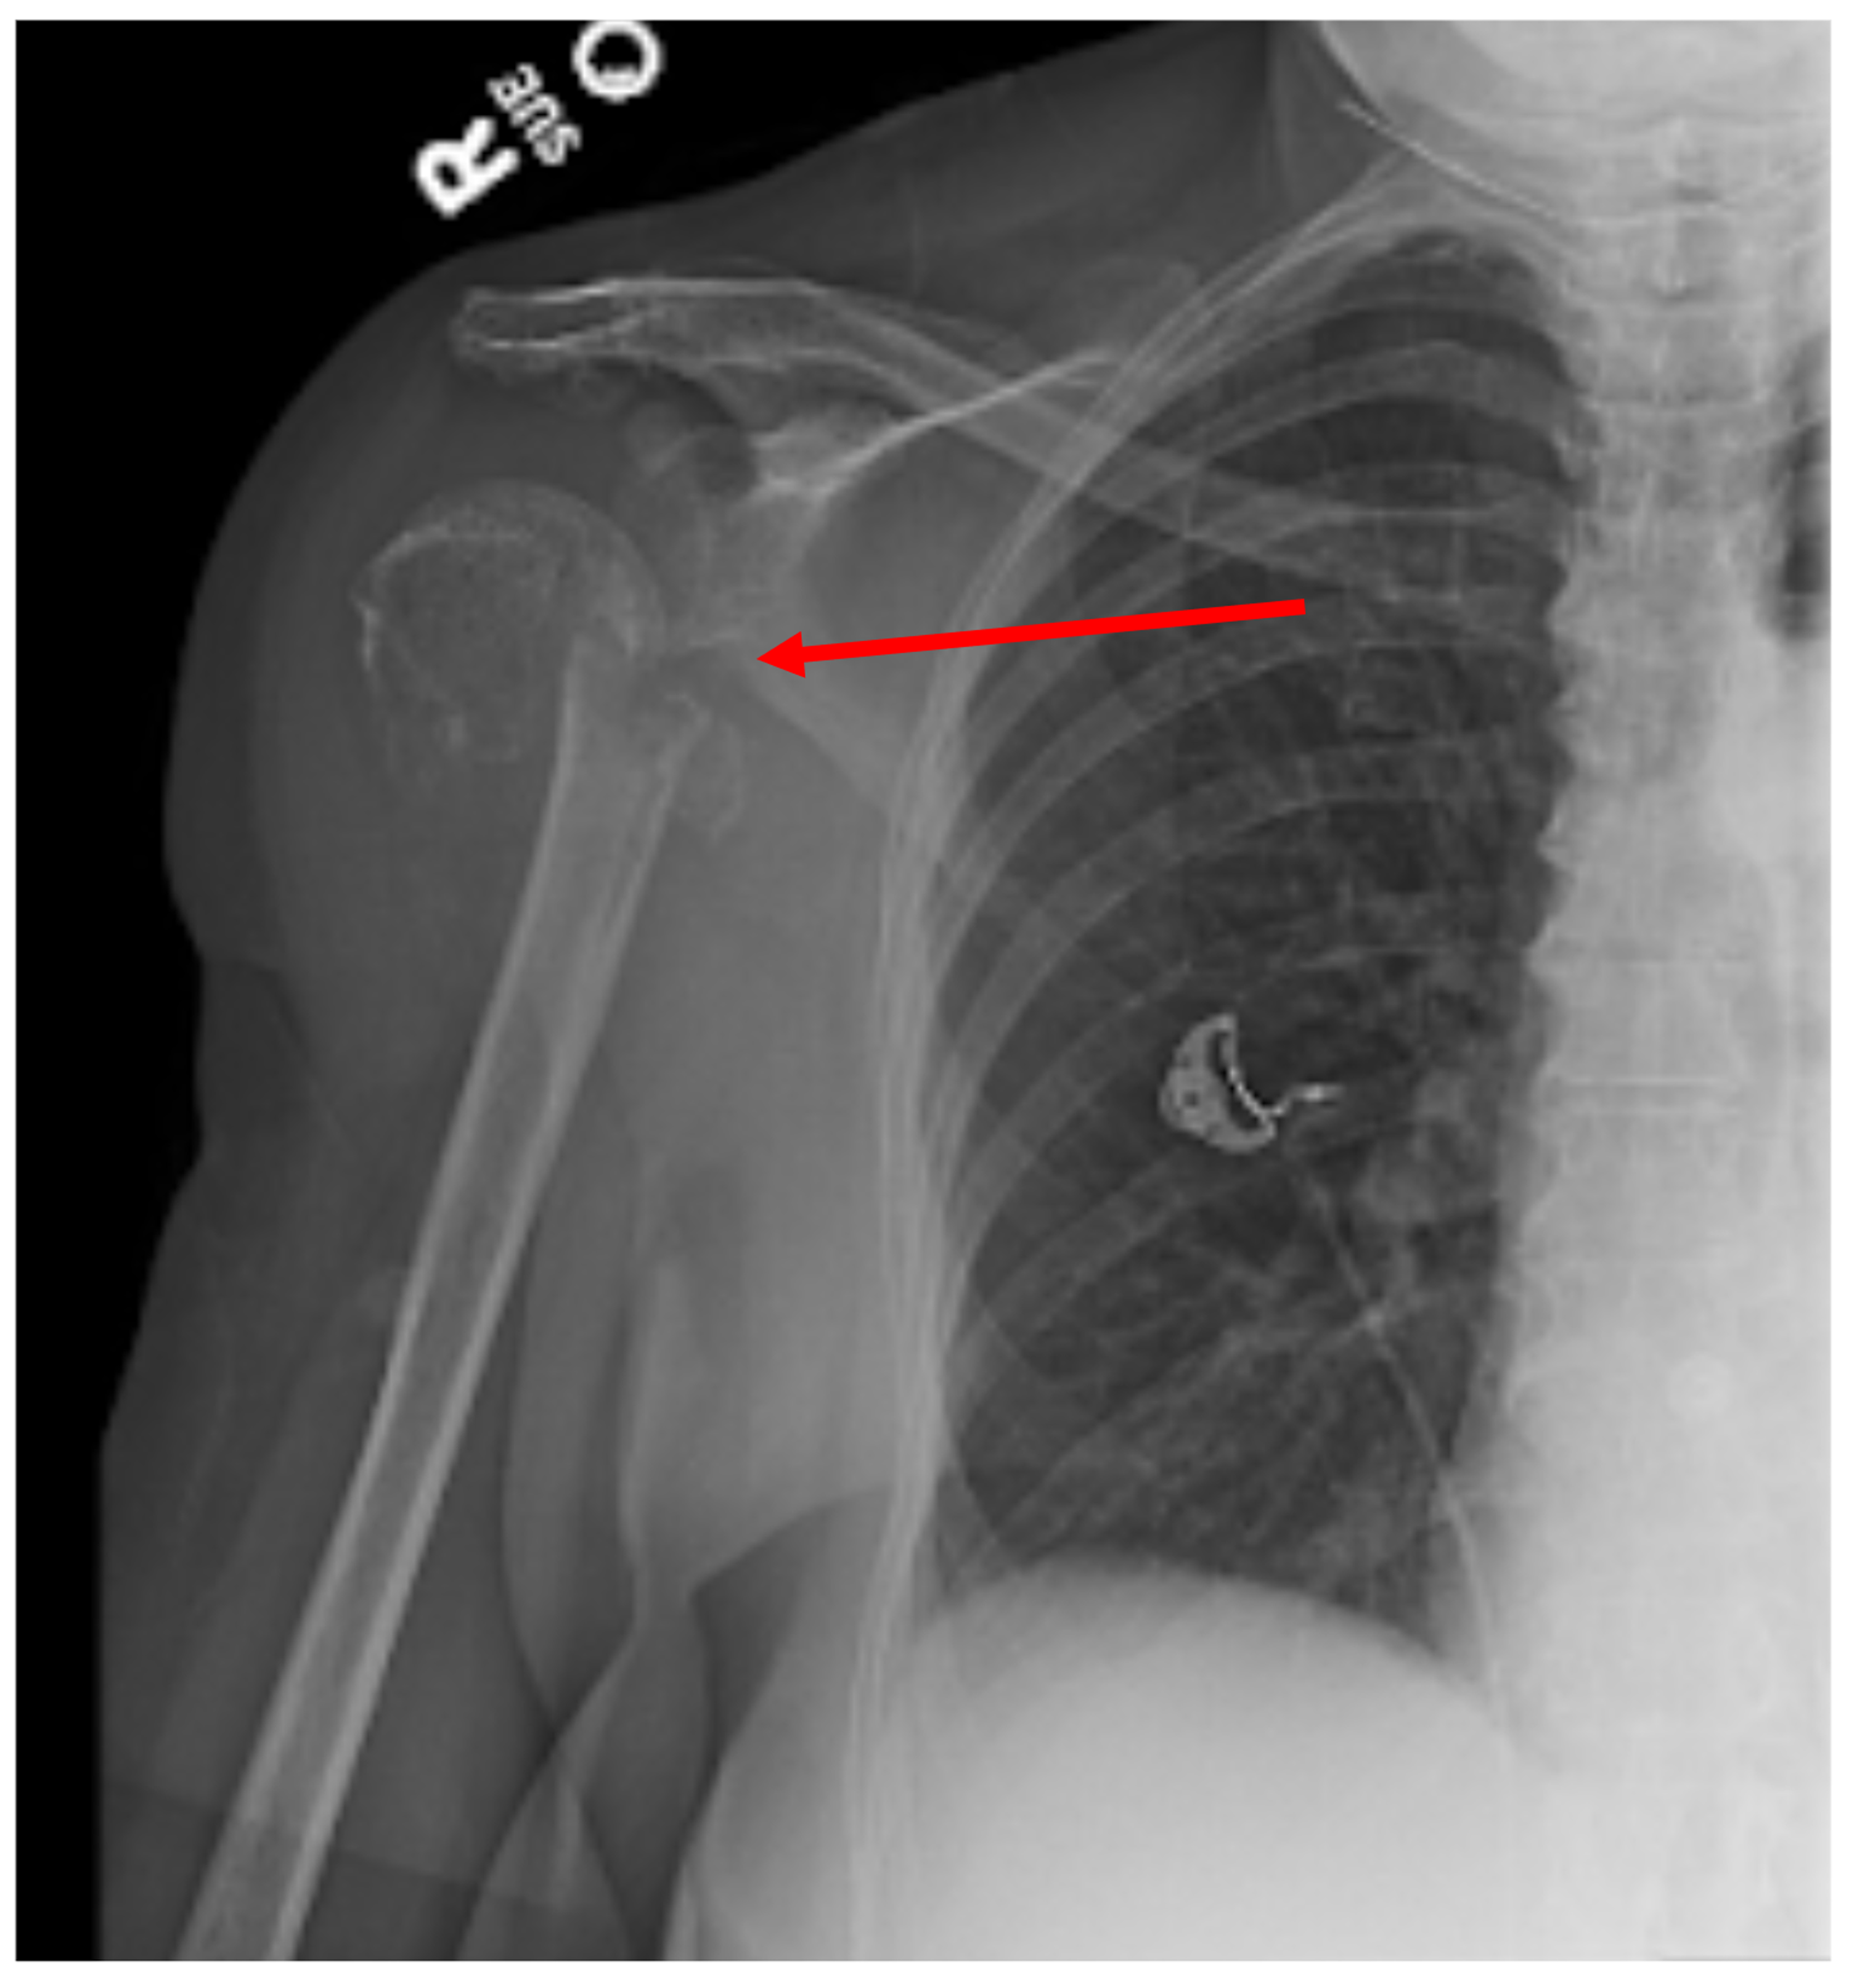

Film Right Shoulder of a 52 Years Old Man with Multiple Myeloma (MM Myeloma Shoulder X Ray The typical appearance of a myeloma. advances in the understanding and treatment of multiple myeloma have led to the need for more sensitive and accurate imaging of. biopsy of the soft tissue mass was performed under ultrasound guidance, with pathology report concluding plasma cell. almost 80% of patients with multiple myeloma will have radiological evidence of skeletal. Myeloma Shoulder X Ray.

Plain radiograph of the right shoulder of a 56yearold man with Myeloma Shoulder X Ray biopsy of the soft tissue mass was performed under ultrasound guidance, with pathology report concluding plasma cell. The typical appearance of a myeloma. ten to forty per cent of multiple myeloma cases are asymptomatic and are incidental diagnoses. advances in the understanding and treatment of multiple myeloma have led to the need for more sensitive and accurate. Myeloma Shoulder X Ray.